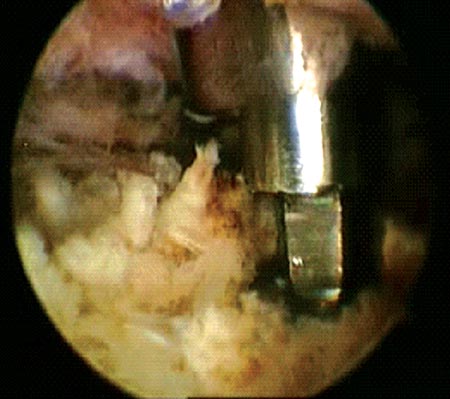

Figura 1C: Espacio subacromial. Reducción artroscópica fractura del troquíter. Se observa línea de fractura./ Figura 1D: Osteosíntesis artroscópica con tornillos canulados de 3.5 mm./ Figura 1E: Reducción y ostesíntesis con 3 tornillos canulados de 3.5 mm. Flecha: pérdida de hueso. Reparación de Bankart y SLAP asociada.

Si la reducción de los fragmentos es correcta en las imágenes por radioscopía, la fijación temporal de los fragmentos óseos con clavijas percutáneas es llevada a cabo. Posteriormente y según el tamaño de los fragmentos se utilizan tornillos canulados de 2.7 mm, 3,5 mm y/o 4.5 mm. Es importante remarcar nuevamente la no resección de los tejidos blandos (manguito rotador) de los fragmentos óseos. En 4casos de fracturas conminutas la reducción y osteosíntesis de los fragmentos fue lograda a través de los tejidos blandos y no del propio tejido óseo. Si la reducción de los fragmentos no es correcta la inspección del lecho de la fractura, primero a nivel articular y luego a nivel subacromial, es llevada a cabo con el fin de facilitar la misma mediante la remoción de tejidos interpuestos. En todos nuestros pacientes fueron colocados no menos de 3 tornillos de fijación (Fig. 1 y 2).